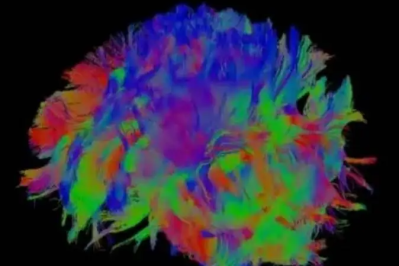

【高尚病例】MRI-DTI(3.0T 磁共振弥散张量成像)应用